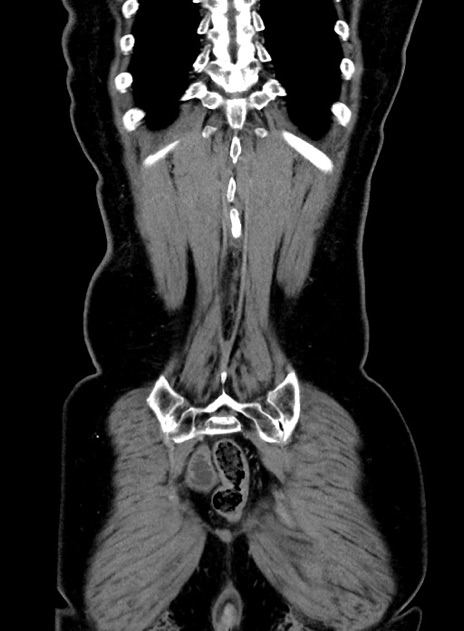

症例9(冠状断像)

症例

【症例】 60歳代女性

【主訴】むかつき、みぞおちの痛み

【現病歴】3日前よりむかつきがあり、食事がとれない。

【既往歴】糖尿病

【身体所見】発熱なし、心窩部圧痛軽度あるも、腹膜刺激症状なし。

【データ】WBC 7400、CRP 1.92